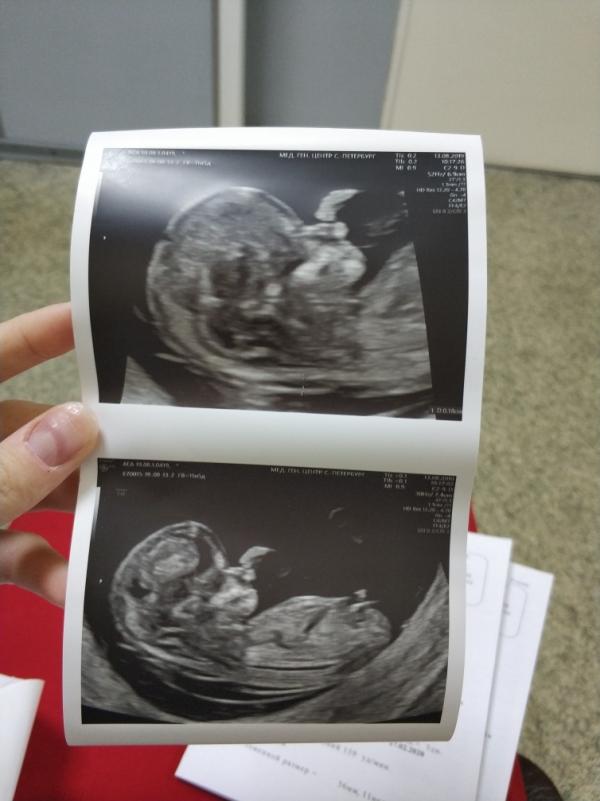

Отзыв про первый скрининг, может кому пригодится инфо :)

Неделю назад, на сроке 11 недель 6 дней ходила в МГЦ на Тобольской, платно к Махаевой Н.Н. (узист высшей категории, к. м.н.)

Доктор делает измерения в своем темпе и диктует их медсестре, и по ходу всё рассказывает нам. Считает руки, ноги, пальцы, органы. Смотрит кровоток.

Полностью прошлась по всем плоскостям, по всем органам.

Пересмотрела дома диск, там доктор оказывается отмечала цифрами прям на экране то, что исследовала. Под этими же цифрами в заключении есть расшифровка. Например желудок и почки под номерами 18 и 21. То есть я могу по УЗИ посмотреть сама, где что. Очень интересно, на самом деле 😀

P.s. Сначала я думала, что на фотках нос)) решила, что шнобель Ого-го, в мужа 🤣 оказалось, что это рука, а нос нормальный.. пока 🙈

@stepler хее) ну, поглядим! Мы пока от первого скрининга не отошли - там космос, конечно! Вроде 5см, а уже человек с пальцами 😯